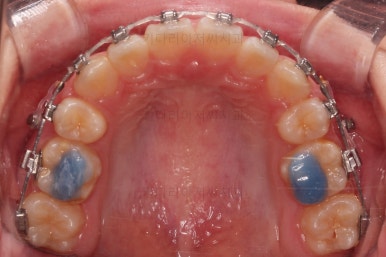

부산덧니교정 마무리를 한 모습인데요.

가지런한 모습 좋고, 교합이나 중앙선 등 매우 잘 맞네요.

치열, 교합, 악궁의 형태 매우 좋아졌어요.